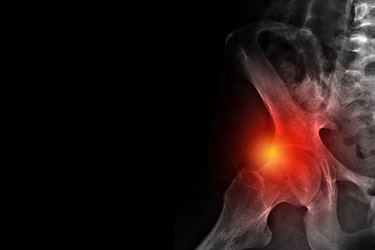

Impacto Femoroacetabular (IFA): guia sobre causas, sintomas e tratamento

O Impacto Femoroacetabular (IFA) é uma das principais causas de dor no quadril em jovens e atletas. Trata-se de um contato anormal entre a cabeça do fêmur e o acetábulo, que pode levar ao desgaste precoce da articulação se não for diagnosticado e tratado corretamente.

O Impacto Femoroacetabular ocorre quando há um “atrito ósseo” anormal entre as estruturas do quadril durante movimentos como flexão e rotação. Esse contato repetitivo pode lesar o labrum (cartilagem que reveste o acetábulo) e acelerar o desgaste articular.